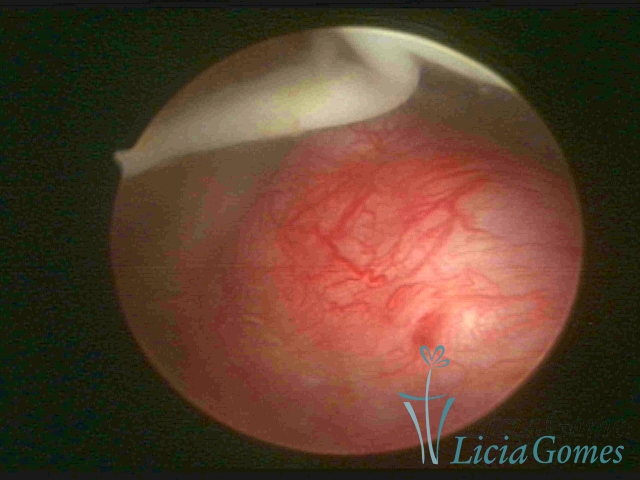

Mirena device® and a submucous myoma